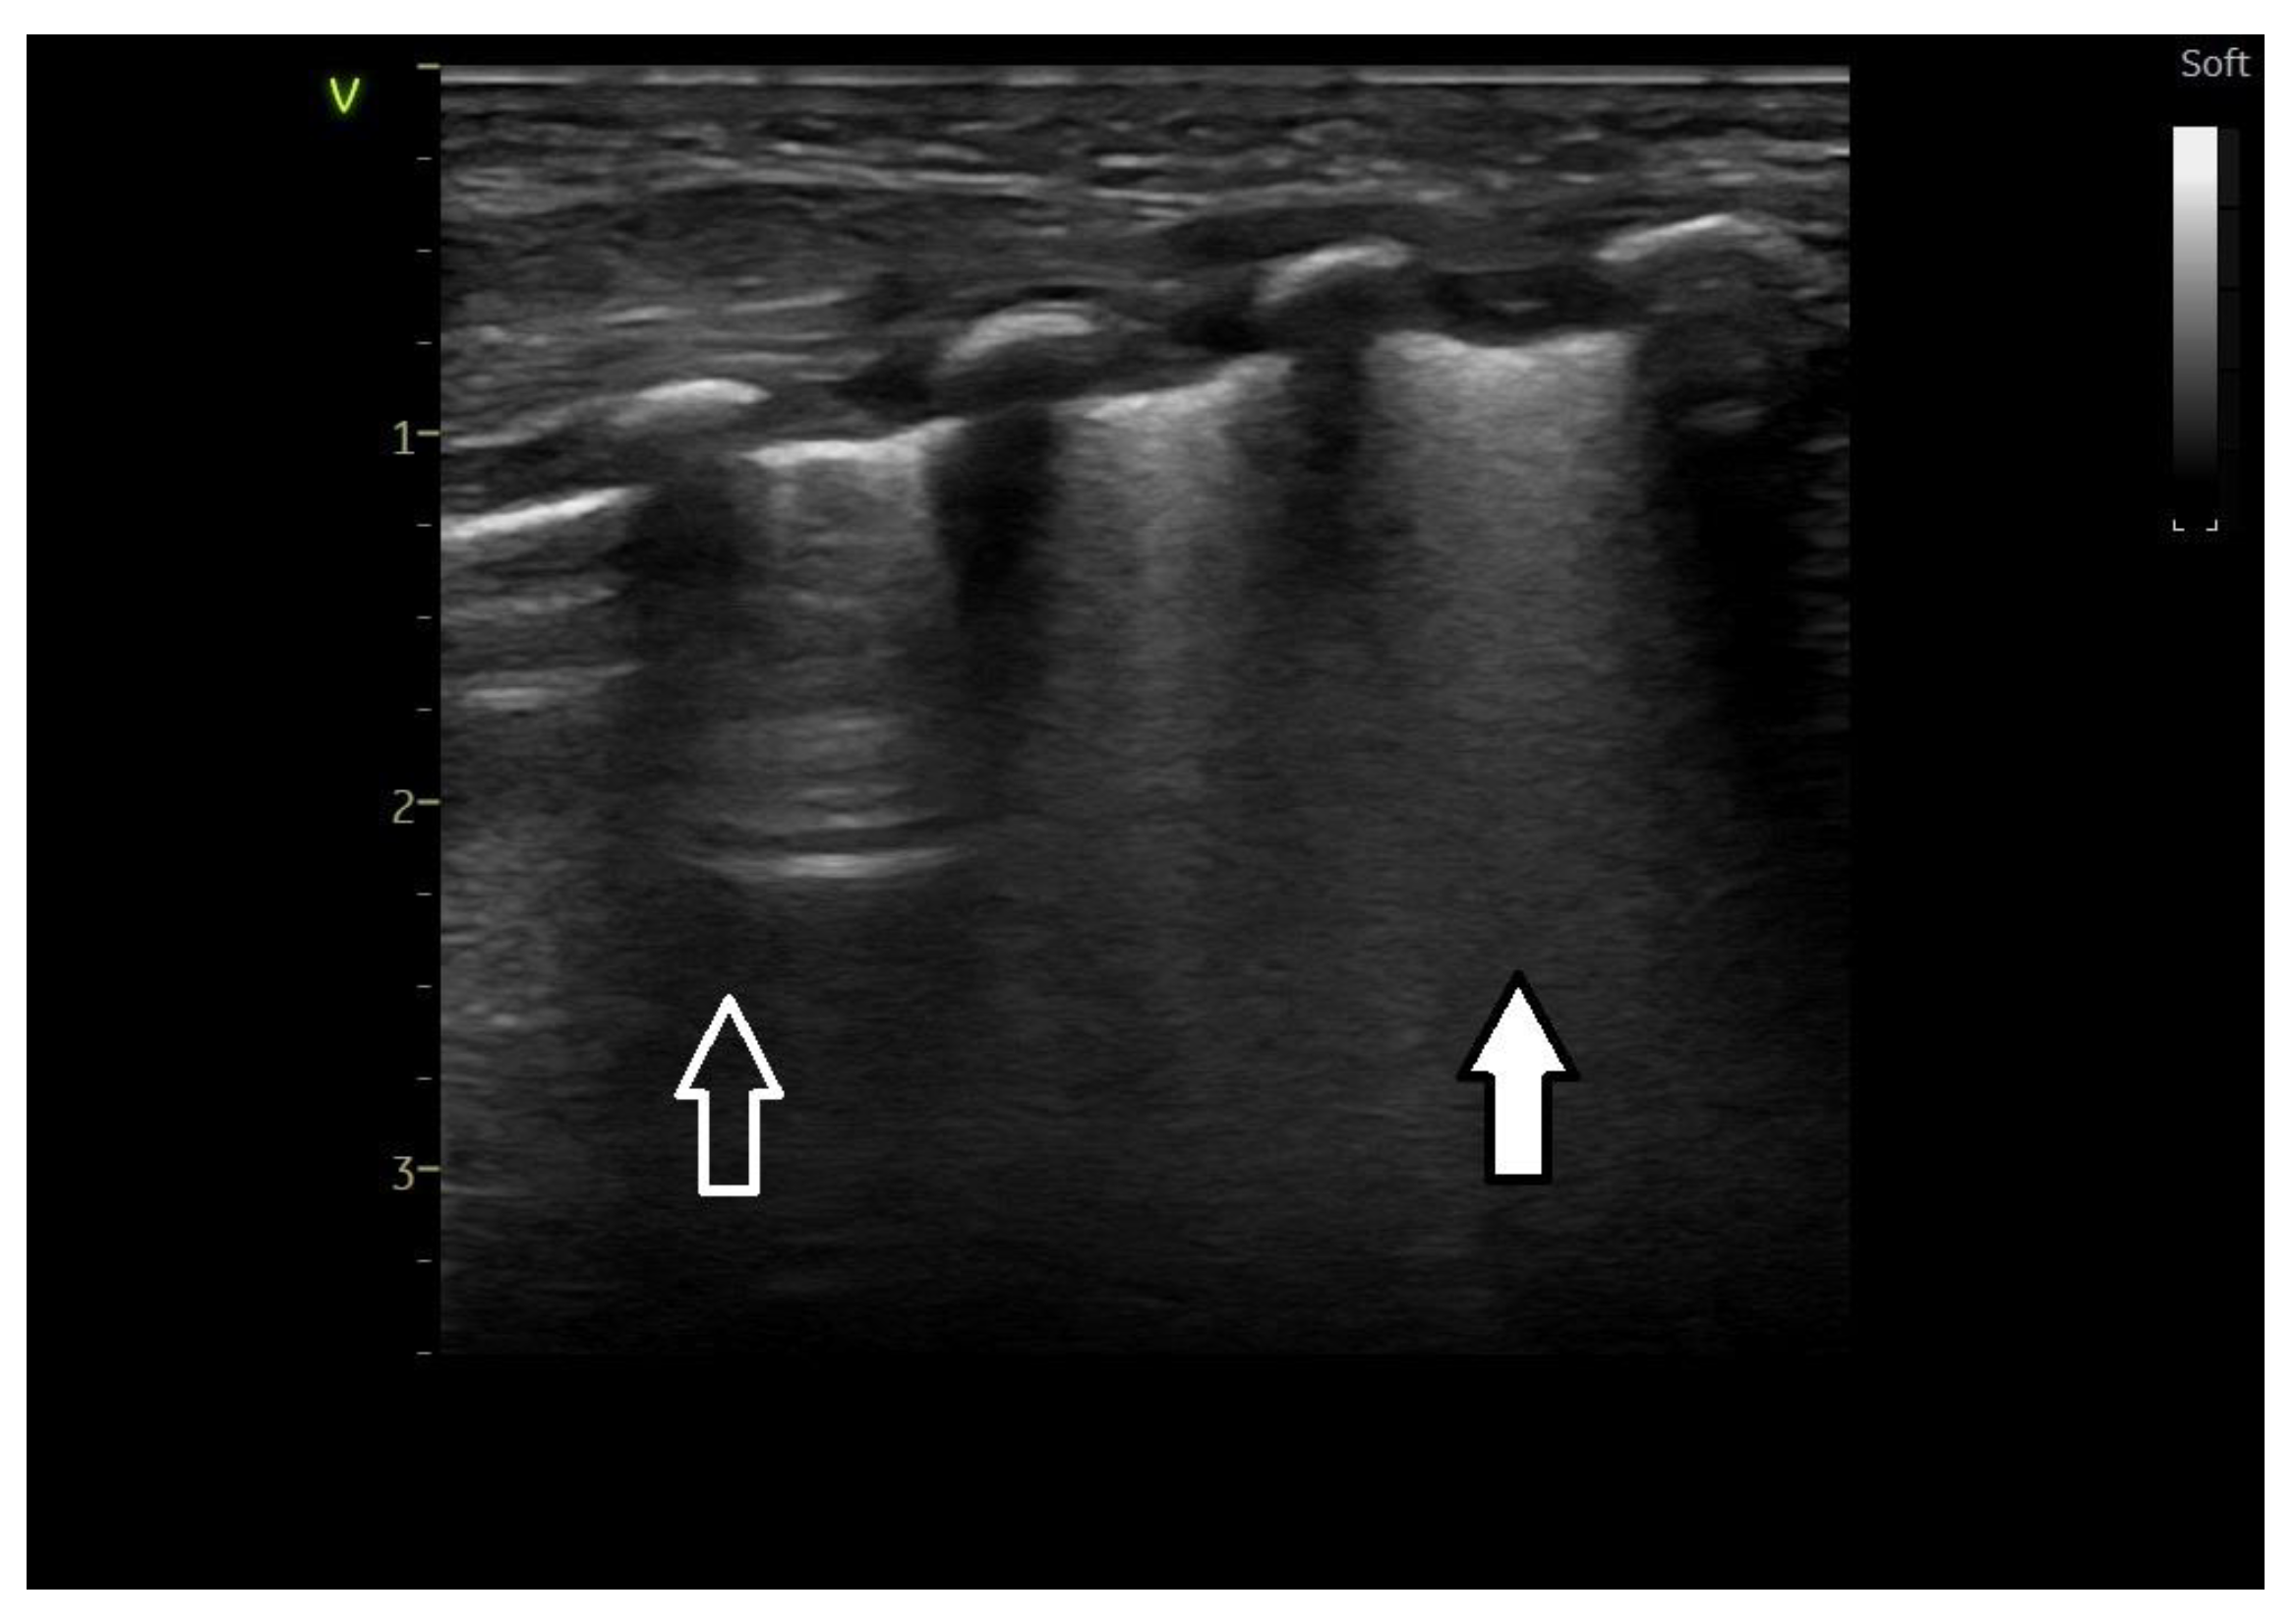

Lung ultrasound